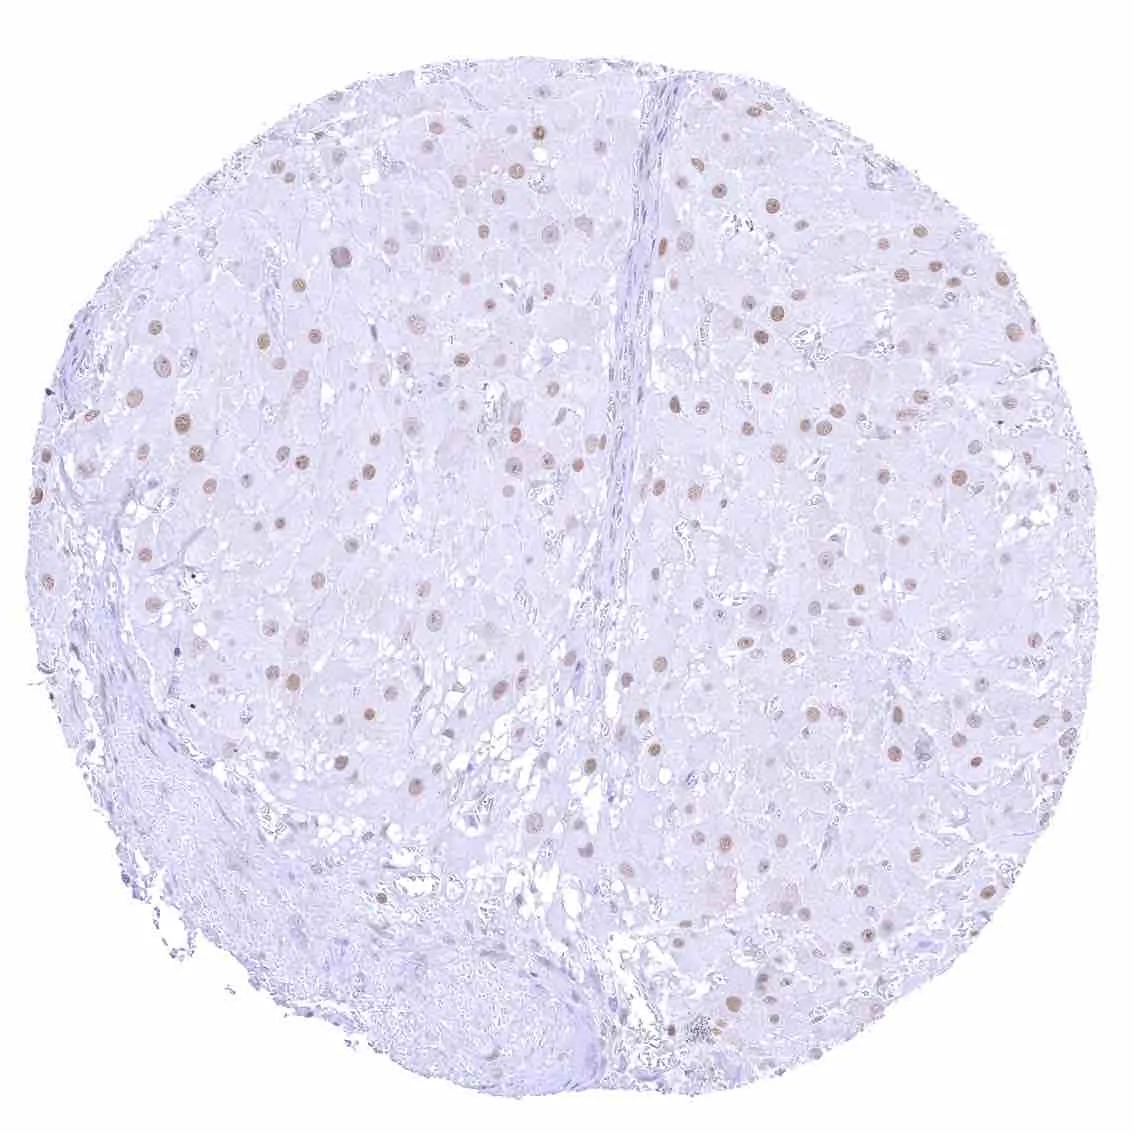

Liver – p27 staining is rare or absent in hepatocytes.